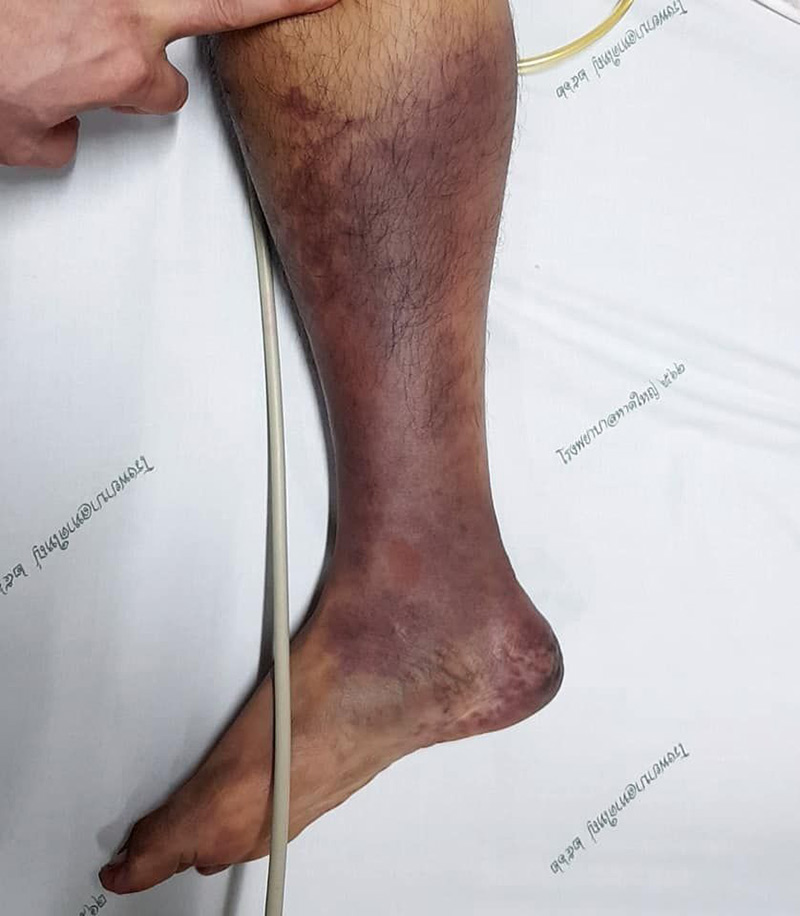

และหลังจากนั้นอีก 1 วัน คนไข้คนเดิมก็ได้กลับมาอีกครั้ง เพราะปวดจนทนไม่ไหว แต่รอบนี้อาการหนักกว่าเดิม เท้าดำไปหนึ่งข้าง พร้อมยกมือไหว้ขอให้ช่วย แต่อาการล่าสุดพบว่า เนื้อขาขวาตายและมีสีดำแล้วต้องตัด ส่วนขาซ้ายก็อาการหนัก ทางแพทย์จึงระดมเจ้าหน้าที่ช่วยกันอย่างเต็มที่ โดยใช้เวลาในการผ่าตัดนานกว่า 8 ชั่วโมง จนสามารถรักษาขาซ้ายเอาไว้ได้ ไม่ต้องถูกตัดขาทั้ง 2 ข้าง